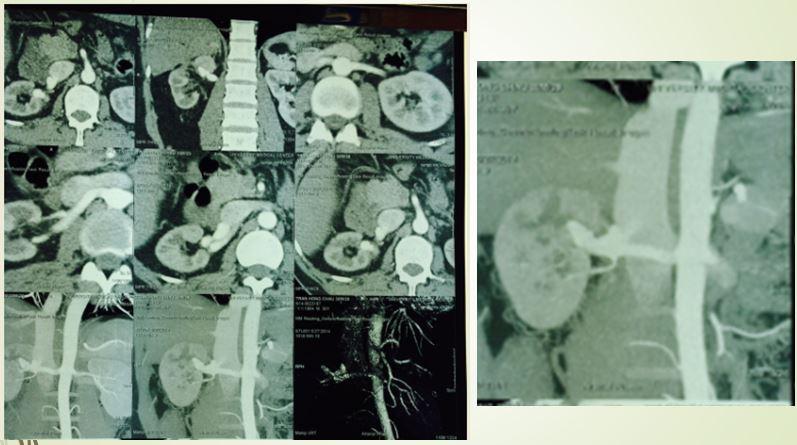

Ca lâm sàng thứ 2 là một bệnh nhân nam 63 tuổi, vào viện vì đau bụng, tiểu máu từng đợt… trước đó, ông đã đi khám từ Bắc chí Nam mà không nơi nào tìm ra hướng giải quyết cho tình trạng của mình. Tại bệnh viện, các bác sĩ đã tìm thấy nguyên nhân là bệnh nhân có rò động tĩnh mạch thận lưu lượng rất cao. Để khắc phục tình trạng này, BS Trần Chí Cường đã can thiệp, dùng bóng để giảm dòng chảy vào động mạch thận để có đường vào sâu hơn, bơm keo gây tắc vị trí thông động tĩnh mạch.

Kỹ thuật dùng bóng kiểm soát dòng chảy và bơm keo

Sau gây tắc bằng keo và bóng

Chỉ trong 24 giờ sau can thiệp, nước tiểu của bệnh nhân trong vắt, trở lại cuộc sống bình thường.

Trường hợp thứ 3 là một lão nông 75 tuổi ở Tiền Giang, 1 năm trước ông sờ thấy một khối gì đó căng ở vùng trên rốn, không đau, đi khám nhiều nơi vẫn chưa biết chính xác đó là gì, cũng không có tiền căn chấn thương vùng bụng. Lần đó ông nhập viện BV Đại học Y dược TPHCM vì đau bụng vùng thượng vị. Các bác sĩ nhìn vùng thượng vị bệnh nhân thấy có khối phồng lên da, sờ thấy căng chắc, có mạch đập, kích thước khoảng 7cm, không di động, ấn đau, không nghe thấy âm thổi. Bụng dưới mềm, xẹp, không điểm đau.

Hình ảnh CT cho thấy túi phình mạch máu khổng lồ trong gan, sát thành bụng

Hình ảnh CT cho thấy một túi phình động mạch gan chung dọa vỡ. Các bác sĩ hội chẩn, nhận định trường hợp này bệnh nhân tuổi cao, vị trí và kích thước túi phình cũng gây khó nếu mổ. BS Cường được mời can thiệp, quyết định gây tắc động mạch gan chung. Sau đó bệnh nhân không bị suy gan hay triệu chứng gì bất thường.

Hình ảnh sau can thiệp, túi phình “biến mất”

Bệnh nhân hết đau bụng, chức năng gan bình thường và tránh được ca phẫu thuật gan ở độ tuổi 75.